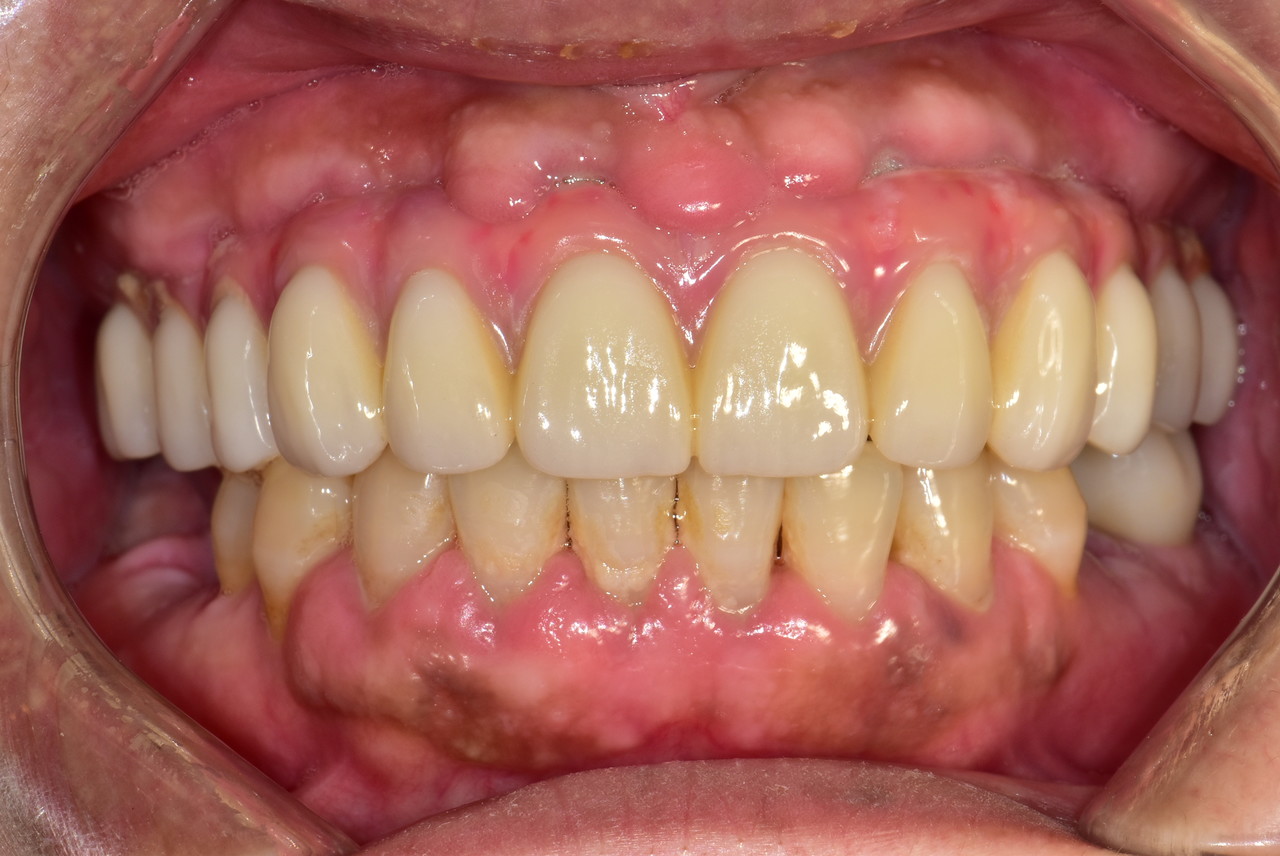

잇몸이 붉지 않고, 연분홍빛을 띠며 단단하게 치아를 감싸고 있습니다. 엑스레이 에서는 치아 뿌리를 따라 잇몸뼈가 치아 경계선 바로 아래까지 촘촘하게 유지되 고 있습니다.

잇몸이 붉지 않고, 연분홍빛을 띠며 단단하게 치아를 감싸고 있습니다. 엑스레이에서는 치아 뿌리를 따라 잇몸뼈가 치아 경계선 바로 아래까지 촘촘하게 유지되고 있습니다.